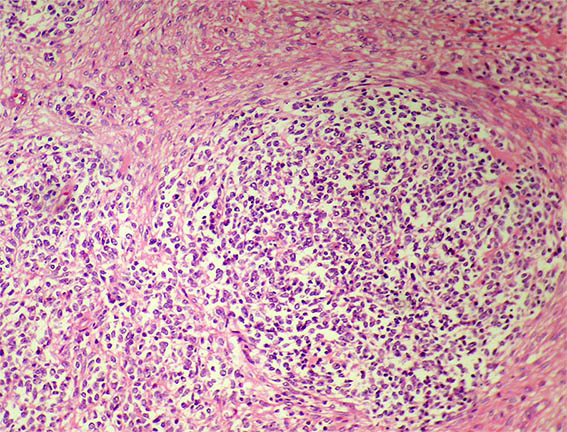

Figure 2. Closer image.

H&E, X100.